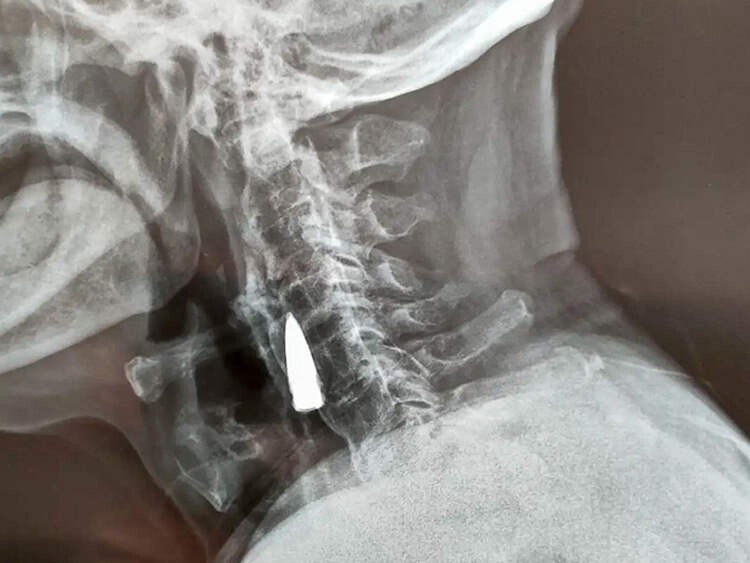

Після падіння з балкона свого будинку в китайській провінції Шаньдун, Чжао Хе, гніваючи на свій поважний вік, почував себе нормально - по принаймні, як кажуть його рідні, він не повідомляв їм про будь-які симптоми. Болю він не відчував, але через деякий час у ветерана Другої світової війни з'явився легкий дискомфорт у шиї. Син вирішив відвезти його до лікарні на обстеження. Почувши про його падіння, лікарі порекомендували зробити рентген, щоб переконатися, що він не отримав серйозні пошкодження шиї. Однак замість перелому рентген виявив у шиї у чоловіки сторонній предмет, який пізніше ідентифікували як стару кулю.

Сам Чжао вважає, що куля перебувала у його шиї з 1944 року. Очевидно, вона справді потрапила до нього переході через річку. Куля пройшла через ліву частину носа, пробила йому верхню щелепу та вибила кілька зубів, після чого застрягла у шиї. Втім, це лише його здогад.

Вивчивши рентгенівські знімки, лікарі сказали Чжао Хе та його родині, що куля пройшла поряд з деякими великими кровоносними судинами і що, оскільки вона не викликала у нього жодних проблем, краще залишити її, як є. Ветеран війни погодився. «Я був здоровий усі ці роки, тому зараз немає причин щось міняти», - сказав Чжао Хе.